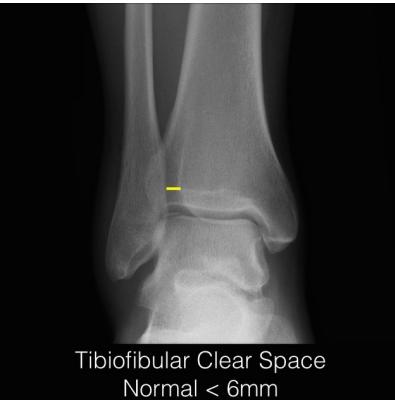

Tibiofibular Clear Space

- Normal: < 6 mm (AP view)

- Pathological: ≥ 6 mm